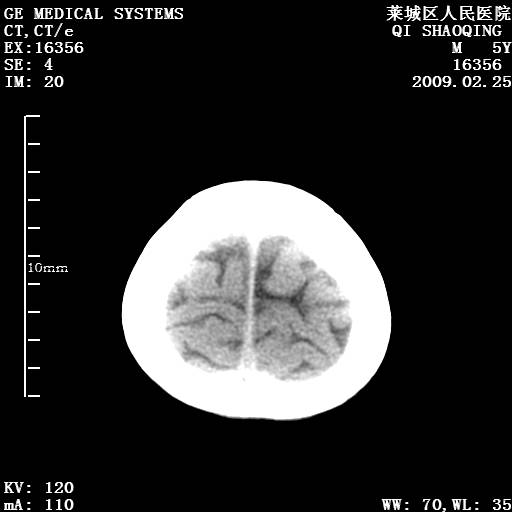

以下是引用wangzhengyuan在2009-2-28 10:22:00的发言:[br]甲状旁腺功能减退引起的脑改变.

以下是引用zsl6918在2009-2-28 10:17:00的发言:[br]首先考虑甲状旁腺功能低下所致,可结合实验室检查明确.另外需除外先天性宫内感染所致.

以下是引用余辉在2009-3-1 9:35:00的发言:[br]患者明显的肢体及智力改变,不支持fahr病,多考虑甲旁低,有可能伴有甲低(呆小症).进一步检查。